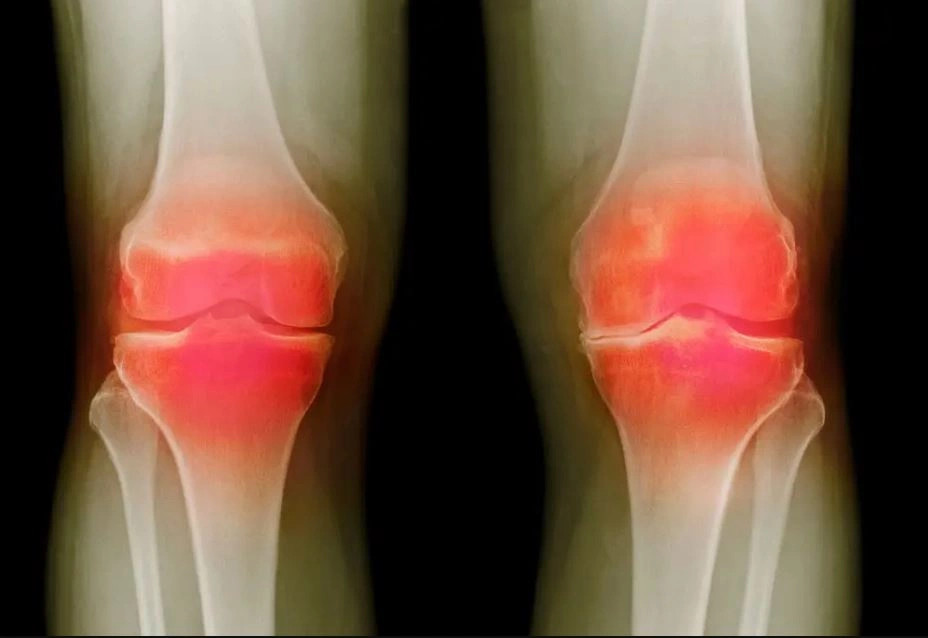

- La osteoartritis afecta a 365 millones de personas en el mundo, siendo una de las principales causas de discapacidad.

La artrosis de rodilla no tiene cura. Punto. Esa es la línea que repiten todos los ortopedistas del planeta y que está escrita con letras de plomo en cada libro de medicina. Es una condena lenta, dolorosa y, hasta ahora, irreversible. Pero resulta que tres laboratorios gringos, con decenas de millones de dólares de una agencia federal llamada ARPA-H, decidieron que ese «punto» era más bien un punto y seguido. Según reporta Emancipacionobrera Blogspot, el proyecto NITRO (Innovaciones novedosas para la regeneración de tejidos en la osteoartritis) ya superó su primera fase preclínica. No estamos hablando de un analgésico más potente ni de una prótesis de titanio más ligera. Estamos hablando de regeneración. De que una inyección en la rodilla pueda, en teoría, reclutar las propias células del cuerpo para reparar el cartílago y el hueso dañados. Suena a ciencia ficción, pero los resultados en animales son tan contundentes que los ensayos en humanos están programados para empezar dentro de 18 meses. Imagínate: 365 millones de personas en el mundo, según los datos del mismo reporte, viviendo con este dolor, y de pronto la promesa de que su rodilla podría sanar, no solo dejar de doler. El impacto sería brutal, no solo en la calidad de vida, sino en toda la industria farmacéutica y de implantes que gira alrededor del manejo paliativo de una enfermedad crónica.